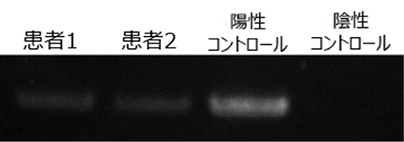

免疫力のない方で問題となる真菌(アスペルギルス感染症)(図7, 8)やニューモシスチス肺炎(図9)に対しては、当科研究室独自に抗体検査や核酸増幅検査を行い、迅速な診断・治療に努めております。国内の研究・検査機関とも協力し、稀な真菌・抗酸菌感染症についても、病原体の同定・診断を試みております(図10) 。

図8. アスペルギルス遺伝子の検出。患者さんの肺胞洗浄液検体よりDNAを抽出し、アスペルギルス遺伝子に特異的なプライマーを使用し、アスペルギルスの遺伝子を同定しました。